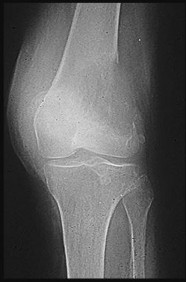

Figures 6a through 6d are the radiographs and T1-weighted sagittal and fat-saturated axial MR images of an otherwise healthy 56-year-old man who has anterior knee pain and intermittent swelling after sustaining a noncontact twisting injury. Low-power and high-power hematoxylin and eosin stained histologic specimens are shown in Figures 6e and 6f. Based on the history, radiographs, CT scan, MR imaging, and histologic findings, what is the most likely diagnosis?

The lesion in the posterior intercondylar knee notch is a benign synovial hemangioma. Intralesional calcifications, classically associated with hemangiomas, are frequently not identified on plain radiographs. The MR imaging reveals a hypervascular lesion with multiple filling defects, with hyperintensity on T2-weighted images and low-to-intermediate signal intensity on T1-weighted images. Histologically, vascular lakes within fine capillaries with a synovium on the surface of the lesion are characteristic of this condition. Many patients with synovial hemangioma have pain, swelling, stiffness, or mechanical symptoms. The correlation of symptoms with the hemangioma for this patient is unclear because there was recent trauma and a concurrent meniscus tear. Simultaneous treatment of both potential sources of pain is typically recommended. As with PVNS, the disease can be localized or diffuse. Surgical excision, either open or arthroscopic, is the recommended treatment. PVNS is the most common intra-articular tumor, but hypointensity in either the diffuse or localized type is characteristic in both T1- and T2-weighted images. Synovial sarcoma, although often found close to a joint, is not characteristically found within a joint.